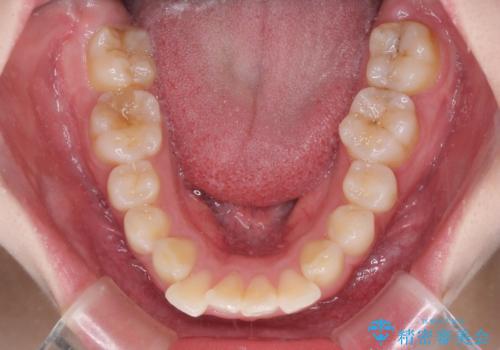

前歯のデコボコをインビザラインできれいに整える

- 前歯のデコボコと上下の隙間を気にして来院された患者様です。

前歯の捻れを改善するとともに、口元が少しでも引っ込むように治療計画を立て、仕上げることができました。